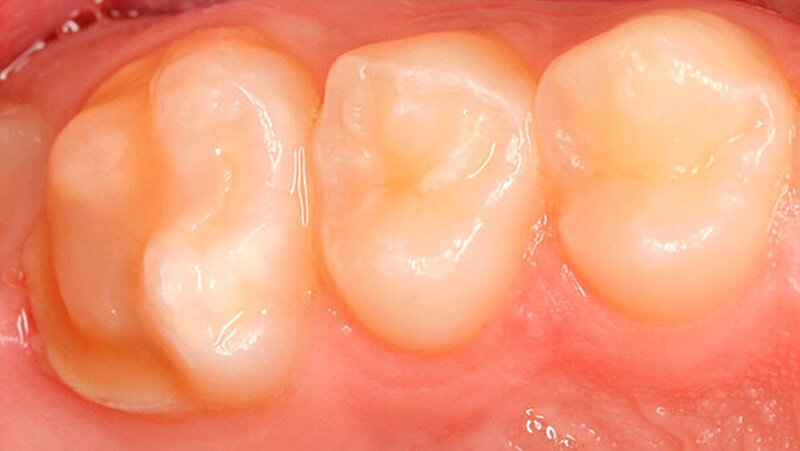

Zusätzlich zeigte der mesio-palatinale Höcker einen deutlichen Schmelzeinbruch (Abbildung 1). Die generelle Mundhygiene war nur mäßig, da insbesondere an den Glattflächen (obere mittlere Inzisivi) auch ohne Anfärbung deutlich sichtbarer Biofilm aufzufinden war (Abbildung 2). Die Zähne 26, 36 und 46 wiesen kaum sichtbare Opazitäten auf, sie waren alle versiegelt (nicht dargestellt).